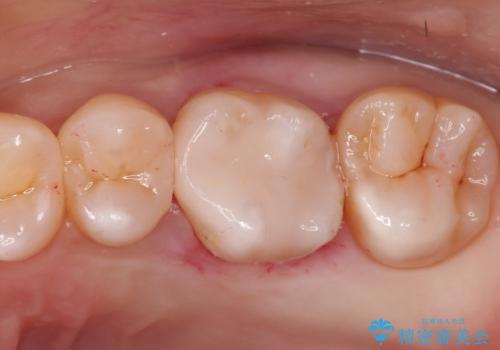

- 矯正終了後にメタルフリーの治療を希望された患者様です。

セラミックインレーにて修復治療を行なっております。

セラミックインレーのセット時にはラバーダムを用い防湿に気をつけて処置をしております。